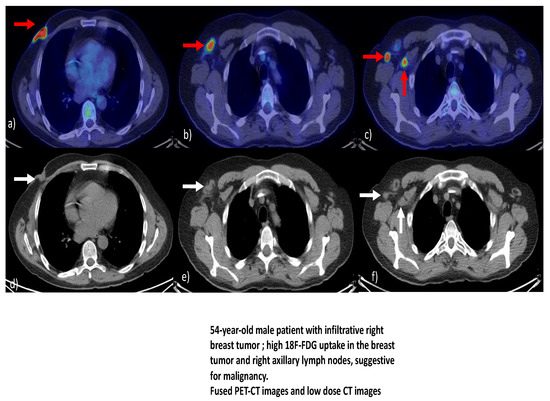

- Dondi, F.; Albano, D.; Giubbini, R.; Bertagna, F. 18F-FDG PET/CT for the evaluation of male breast cancer: A systematic review. Nucl. Med. Commun. 2022, 43, 123–128. [Google Scholar] [CrossRef] [PubMed]